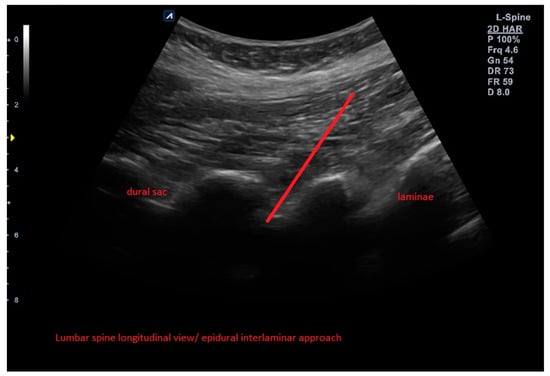

The control group (A) as an active comparator received an ultrasound-guided epidural (intralaminar) injection of Orthokine into the epidural space (interlaminar approach) above the affected segment (Figure 2).

Figure 2.

Example of ultrasound-guided epidural ACS injection with needle trajectory in the control group (A).